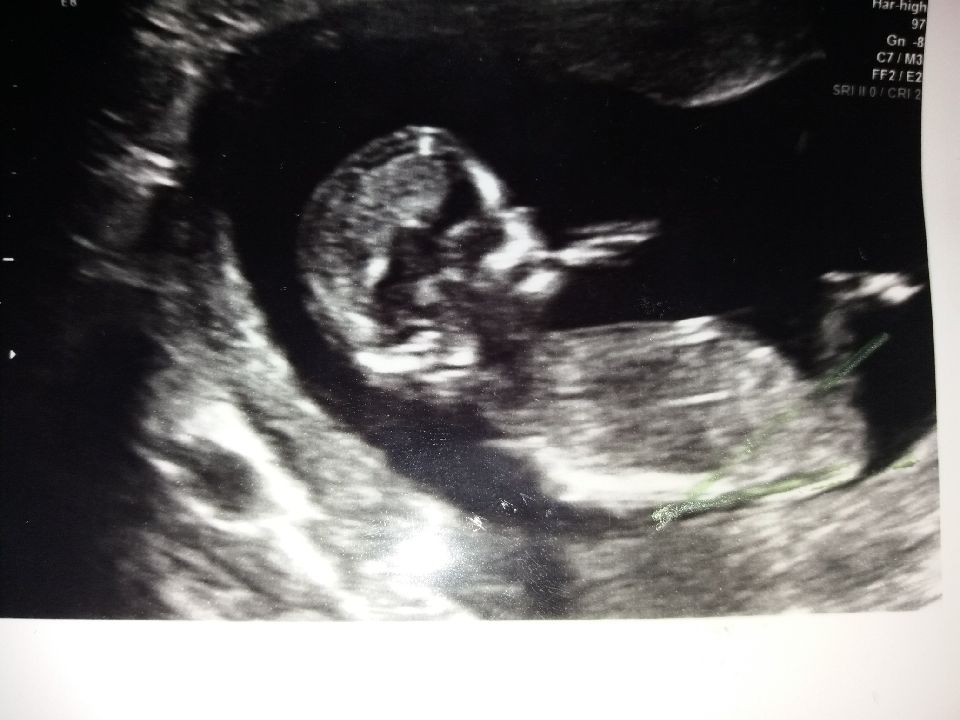

Ultrasound week 13..boy or girl??

Ultrasound from week 13..what do you think? Boy or girl??